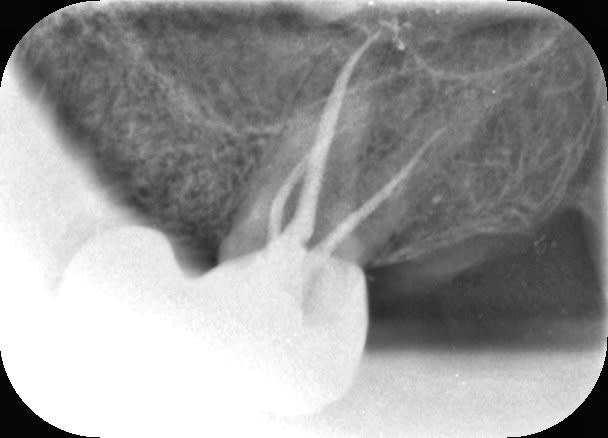

L’apex est là Vulpi . Je sais qu’on n’a plus une très bonne vision avec l’âge mais ensuite faut pas confondre c’est de l’os dense :)

vulpi

25/10/2019 à 09h46

lampadaire skurup écrivait:

-----------------

> L’apex est là Vulpi . Je sais qu’on n’a plus une très bonne vision avec l’âge

> mais ensuite faut pas confondre c’est de l’os dense :)

Mouais... qui vivra verra...